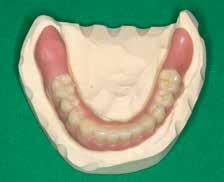

Prothetische Rehabilitation nach Resektion

Der Patient wurde im Zuge der Tumornachsorge wieder an der Universitätszahnklinik Wien vorstellig. Am Beginn der prothetischen Fallplanung wurden montierte Situationsmodelle erstellt und ein aktueller Röntgenstatus erhoben. Intraoral bestätigte sich, dass der resezierte Bereich mittels eines Zungentransplantates gedeckt wurde.

Da der Patient bereits bestehende alte

Modellgussprothesen für den Oberkiefer und den Unterkiefer hatte, wurden diese herangezogen und als Immediatersatz erweitert sowie unterfüttert. Während der Planung entschied sich das behandelnde Ärzt:innen-Team sowohl im Ober- als auch Unterkiefer für eine teleskopierende Metallgerüstprothese. Zahn 11 wurde mittels Adhäsivtechnik aufgebaut und darüber hinaus für Zahn 21 eine Einzelzahnzirkonkrone geplant. Um eine adäquate Retention der Kronen gewährleisten zu können, wurden an fünf Zähnen gegossene Stiftaufbauten eingegliedert (Abb. 6 u. 7).

Nach erfolgter Meisterabformung beider Kiefer erfolgte eine Überabformung der angefertigten Transferkäppchen mit einem individuell angefertigten Abformlöffel. Somit konnte dem zahntechnischen Labor eine präzise Schleimhautabformung zur Verfügung gestellt werden. Insbesondere wurde dabei auf die Detailtreue des resezierten Bereiches im Unterkiefer geachtet.

Anschließend an die Bissnahme mittels Bissschablonen und die gemeinsame Begutachtung der

Wachsaufstellung (Abb. 8–10) erhielt das zahntechnische Labor die Freigabe zur Erstellung der Primärund Sekundärteleskope mit Gerüsten. Diese wurden insbesondere auf ihre Passgenauigkeit und Schaukelfreiheit im Kiefer überprüft. Des Weiteren wurde bei der Erstellung auf eine Unterspülbarkeit des transplantierten Gebietes geachtet. Nach erfolgter Wachsaufstellung auf Gerüst wurde die Fertigstellung der Teleskopprothesen und der Einzelzahnzirkonkrone in

Auftrag gegeben. Für Zahn 11 wurde vom zahntechnischen Labor ein entsprechendes Mock-up mit Schiene zur Übertragung erstellt (Abb. 11–23). Anschließend an die komplikationslose Eingliederung der Arbeit erfolgte eine Kontrolle sieben Tage nach erfolgter Übergabe (Abb. 24, Seite 7). Nach der Durchführung von minimalen Korrekturen an der Okklusion wurde der Patient in den Recall entlassen.•